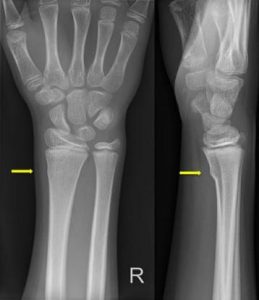

Your child has a small fracture in the lower-arm, a torus fracture. It is a buckle of the bone. This is treated with a brace and a sling.

Your child has a small fracture in the lower-arm, at the level of the wrist.

The torus fracture of the wrist or lower-arm is a common injury in children. The fracture is treated with a brace and a sling.